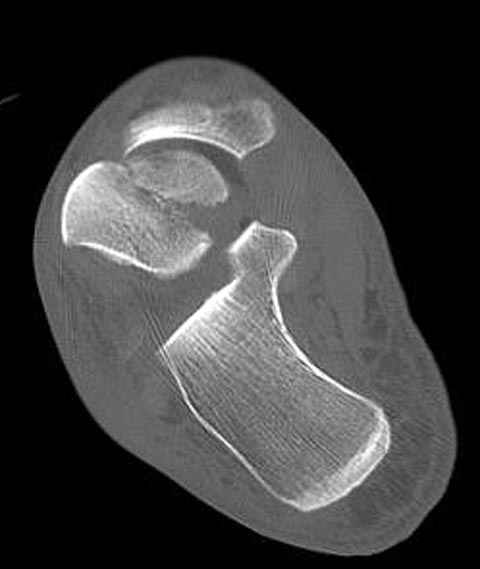

Уважаемые участники русского Ортофорума, поздравляю всех со всеми прошедшими праздниками: Новым годом, Рождеством, Hanukkah, Kwanzaa, желаю участникам всего наилучшего и здоровья.Повреждение таранной кости.Больной 81г автоавария, повреждение таранной кости, здесь снимки. Какие рекомендации?Djoldas Kuldjanov, MDDepartment of Orthopedic SurgerySt. Louis University Medical Center

Вдогонку по поводу перелома таранной кости, больная 81, не страдает диабетом, перелом закрытый, в первый же день поступления ограничились временным наружным фиксатором (как на снимке).

Планировалась открытая фиксация после спадения отека, но больная пожелала лечиться по месту жительству в другом штате..

Из-за отека на стопе тактика лечения у всех была

одинаковая: временная наружная фиксация до спадения отека, при изолированных переломах они выписывались домой и через дней 7 госпитализировались на оперативное лечение.

Примеры на снимке...